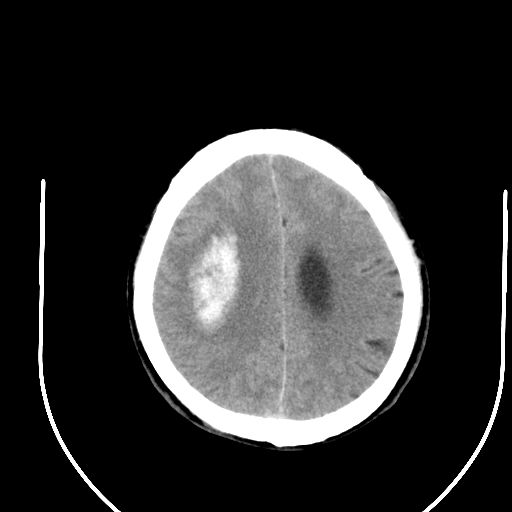

右侧基底节区脑出血并破溃入脑室。

1右侧基底节脑出血伴脑干出血并破入脑室系统脑疝形成2梗阻性脑积水

1)右侧基底节脑出血伴脑干出血并破入脑室系统。2)大脑镰下疝。3)梗阻性脑积水。

1、右侧基底节脑出血伴脑干出血并破入脑室系统。

2、大脑镰下疝。

3、梗阻性脑积水。